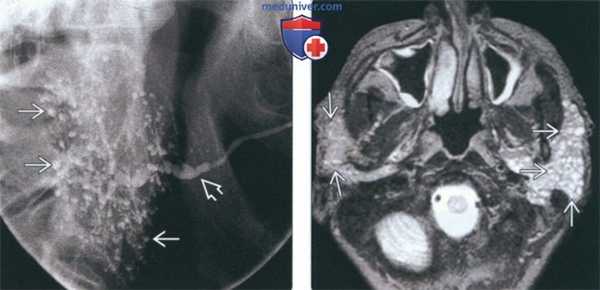

• Традиционная сиалография:

о Чередующиеся участки стеноза и расширения протока железы (по типу ожерелья)

о Формирование расширенных ацинусов (по типу яблони)

• МР-сиалография вытесняет традиционную сиалографию

(Слева) Сиалограмма околоушной железы в боковой проекции, на которой определяются участки расширения и стеноза протока Стенсена (по типу ожерелья). Внутрижелезистые протоки разветвлены, содержат кистозные полости (в виде яблони). Подобные находки могут встречаться при любом хроническом сиалоадените, но более всего характерны для синдрома Шегрена.

(Справа) МРТ Т2ВИ FS, аксиальная проекция. В обоих околоушных железах определяются гипереинтенсивные образования, которые представляют собой кистозное расширение протоков околоушной железы при синдроме Шегрена. Тем не менее, такая МР-картина неотличима от лимфоэпителиальных образований при ВИЧ. (Слева) КТ с КУ, аксиальная проекция. Жировая инволюция обеих околоушных желез, которые имеют многодольчатое строение. В толще желез множественные кальцификаты. Участки отечной железистой ткани, в которой встречаются фрагменты жировой клетчатки и кальцификаты, характерны для синдрома Шегрена.

(Слева) На традиционной сиалограмме (боковая проекция) определяется распространенная точечная сиалэктазия правой околоушной железы в виде «цветущей вишни» или «фруктового дерева без ветвей». Картина типична для синдрома Шегрена (СШ). Обратите внимание на чередование расширенных участков и стриктур протока Стенсена в виде «связки сосисок» (картина хронической инфекции, сиалодохита).

(Справа) На аксиальной МРТ (Т2 ВИ FS) визуализируются многочисленные мелкие кисты, разбросанные в паренхиме обеих околоушных желез (картина множественных милиарных кист).

(Слева) МРТ Т2ВИ FS, аксиальная проекция. Ткань обеих околоушных желез полностью замещена бесчисленными мелкими кистами. Выраженное увеличение размеров обеих желез. Данная картина характерна для острой стадии синдрома Шегрена.